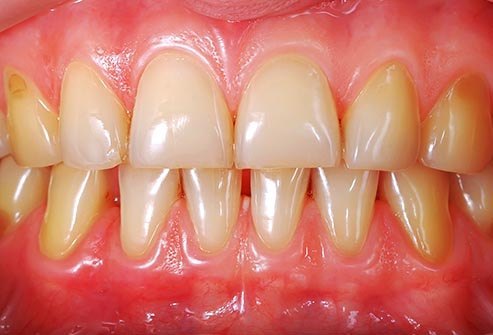

Problemet me Mishra

A rrjedh gjak lehtë nga mishi i dhëmbëve tuaj? A është gjendja për t’u brengosur? A e vëreni tërheqjen nga dhëmbët? Kjo mund të jetë faza e hershme e sëmundjes se mishit të dhëmbëve (gingivitis) ose faza më e avancuar (periodontitis). Një pllakëz e ndërtuar dhe bakteriet e ngjitura poshtë vijës së mishit e shkaktojnë atë. Mostrajtimi i periodontitis mund të shkaktojë humbjen e eshtrave dhe dhëmbët tuaj mund të ndryshojnë ose të bëhen të lëvizshëm. Kjo gjë mund ta bëjë të vështirë përtypjen, madje edhe të folurit. Për të shmangur sëmundjet e mishit të dhëmbëve pastroni dhëmbët me brushë dhe pe, shpëlarni me një gargarë dhe vizitoni dentistin tuaj regullisht për pastrim.